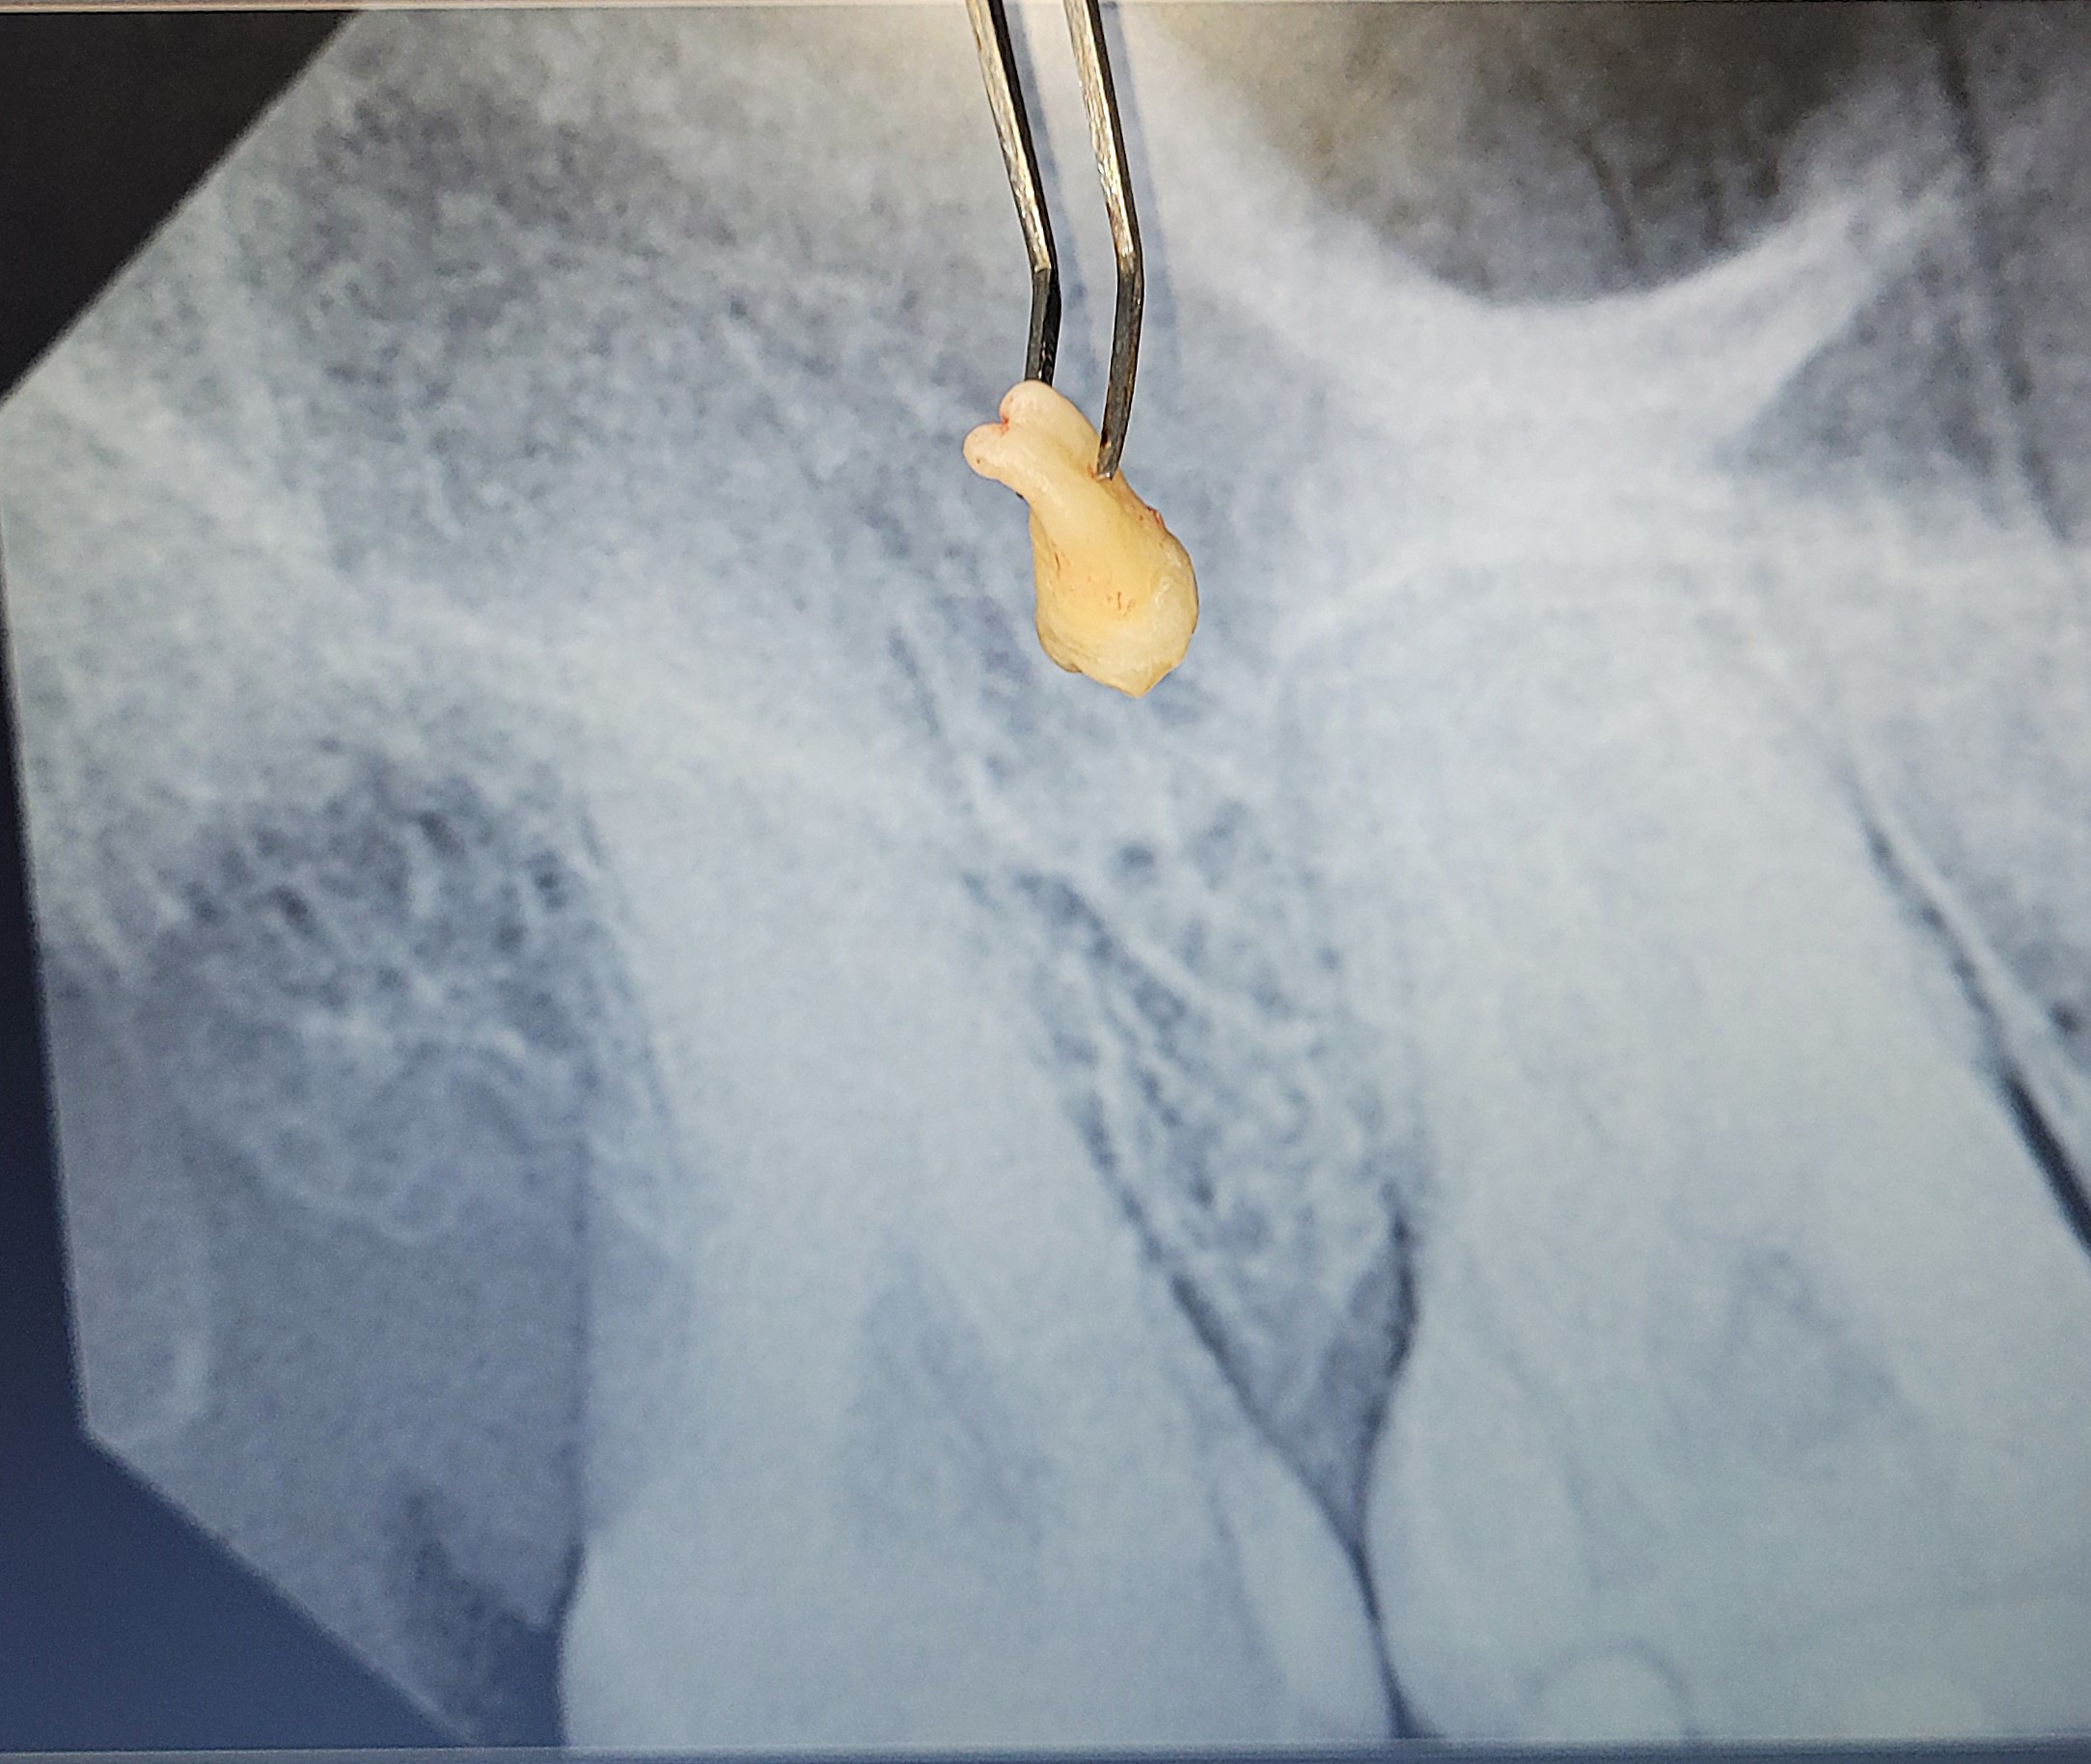

EXTRACTION OF WISDOM TOOTH:-

This case highlights the surgical removal of an impacted tooth, commonly a wisdom tooth that fails to fully erupt. In some cases wisdom tooth is trapped beneath the gums or bone, often growing at an angle and causing pain, swelling, or damage to nearby teeth. A minor surgical procedure is performed under local anesthesia to carefully expose and extract the impacted tooth. Surgical extraction prevents future infections, crowding, or cyst formation. The procedure is safe, effective, and usually completed in a single visit. A necessary step for long-term oral health and comfort.